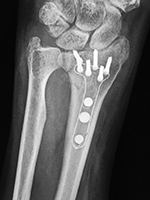

| Locking dynamic compression plate (LCD) and screws transfix a healed distal radius shaft fracture |

| There is also a volar periarticular fixed angle plate and screws with a proximal locking screw that transfixes a new healing distal radial diametaphyseal fracture. From Taljanovic, 2005 |